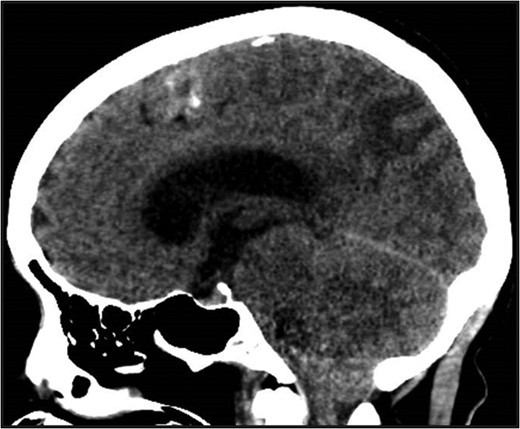

Non-contrast head CT. Non-contrast head CT showing hydrocephalus with tonsillar herniation and vasogenic edema of the parietal and occipital lobes.

While PRES has been associated with sepsis, colorectal cancer and a history of chemotherapy administration; fulminant presentation in the immediate post-operative period in the setting of normotension has not been described. While subtle manifestations were seen in two of the four total perioperative cases identified, these patients exhibited mild to moderate new onset hypertension in the immediate post-operative period [10]. In the case we describe, the patient was obtunded from the immediate postoperative period until diagnosis and subsequent management aimed at reducing intracranial hypertension. We theorize that the systemic vasodilation and capillary leak associated with this patient's abdominal sepsis was exacerbated by the induction of anesthesia and precipitated PRES. Despite her resultant vasogenic edema and intracranial hypertension progressing to tonsillar herniation, timely surgical intervention and optimal medical management facilitated a complete neurologic recovery.